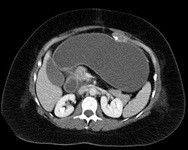

CT of the abdomen in the same patient reveals a tremendously dilated gastric remnant. With CT guidance, a dilated remnant is easily accessed percutaneously

From collection of Daniel M. Herron, MD